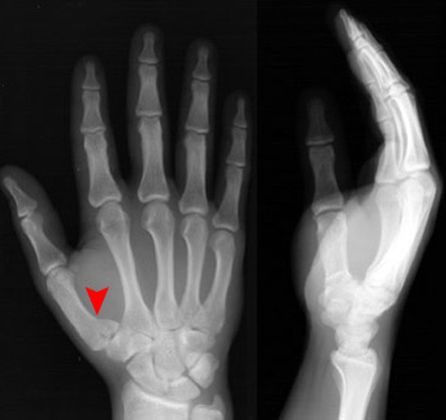

拳击手骨折

握拳撞击

通常发生在第五掌骨

Bennett Fracture

第一掌骨基底部

关节内骨折伴脱位–背侧半脱位

轴向压力